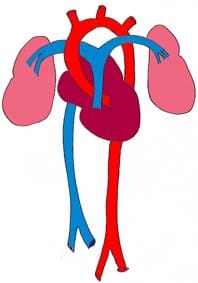

Durante il mese precedente, la circolazione sanguigna non era in grado di essere autonoma in quanto l’embrione non poteva produrre cellule sanguigne. ...